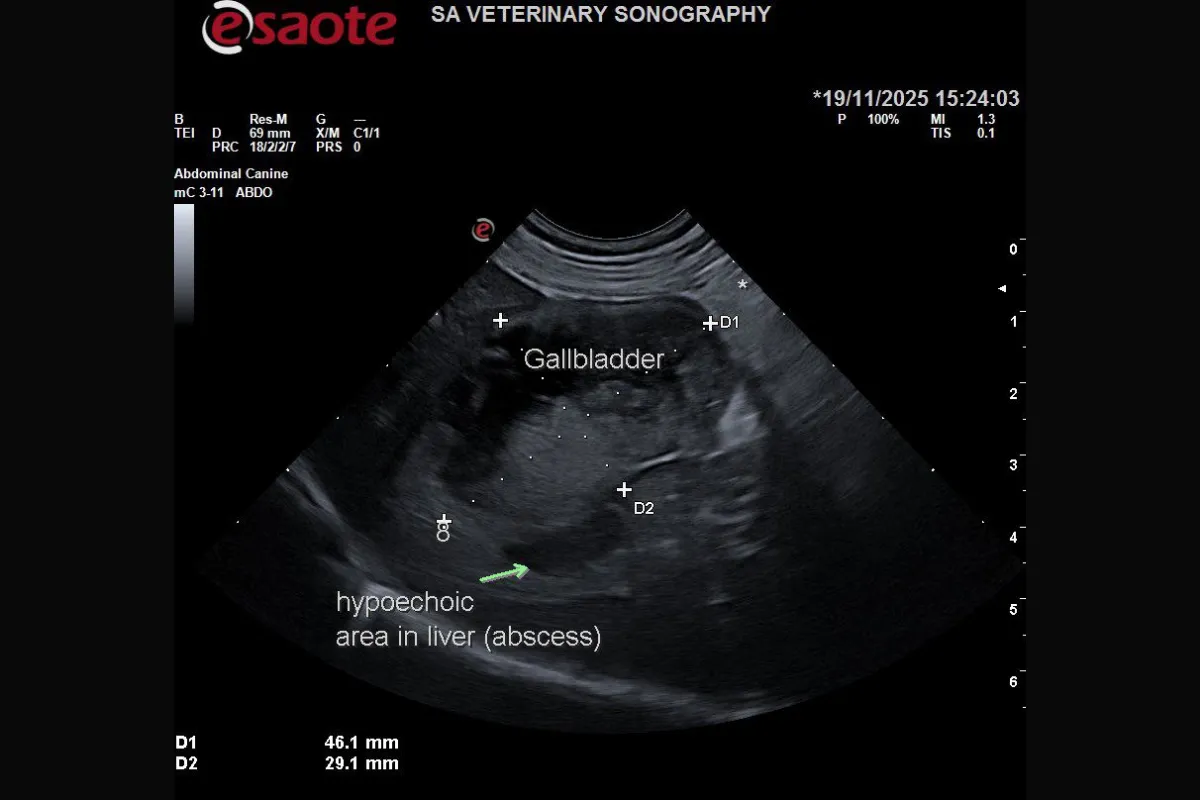

The gallbladder was severely abnormal: distended, thick-walled, and containing a mix of organised and motile sludge. Significantly, a gas artefact was visible arising from the gallbladder wall, an alarming finding consistent with emphysematous cholecystitis, a life-threatening infection that risks rupture and fatal peritonitis. Adjacent to the gallbladder, a poorly defined hypoechoic lesion within the liver suggested a possible abscess.

These findings confirmed a severe gallbladder infection, likely associated with an atypical form of mucocele despite the absence of the classic kiwi-fruit pattern.